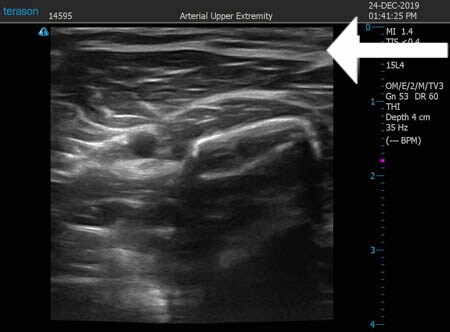

いつものように3Dタッチビュー(超音波)で

皮下脂肪層を評価してみましょう。

右二の腕

↓ ↓ ↓